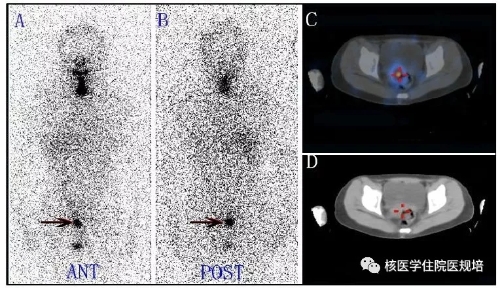

Rx-WBS可出现假阴性或假阳性显像结果。假阴性显像结果主要原因考虑为病灶在平面显像时的重叠干扰。Rx-WBS假阳性显像一般有以下几种成因:1.钠碘转运体(NIS)的表达2. 131I标记的甲状腺激素的代谢3.放射性131I在体液的滞留4.在炎症组织中滞留和吸收5.生理性分泌物的污染等。Rx-WBS假阳性显像全身均可能出现,包括头颈部、胸腹部、盆部、四肢等部位。其中,盆腔假阳性女性患者多见。DTC肿瘤转移到盆腔的概率很低,但当患者全身显像出现盆腔异常131I摄取时,往往可提示其他的临床信息,如子宫(子宫肌瘤、子宫内膜腺肌病、子宫内膜增厚、宫内绝育器、宫颈慢性炎症等)、卵巢(卵巢巧克力囊肿、卵巢甲状腺囊肿、卵巢腺瘤等)、膀胱、肠道、输卵管结扎等病生理情况(图4、图5、图6)。

图4 子宫肌瘤致异常131I摄取